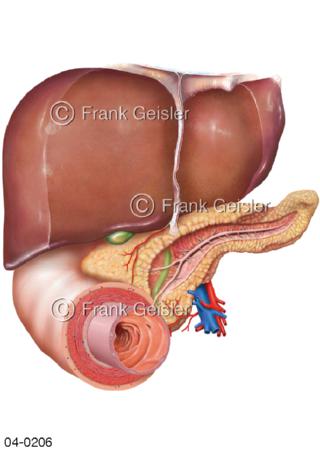

Bildergalerie Topografie Organe

Bilder zur topografischen Anatomie, die Lage der Organe und die Strukturen nach ihren räumlichen Lagebeziehungen zueinander, Übersicht der inneren Organe im Kopf und im Rumpf, Topografie der Organe im Brustraum (Thorax) und im Bauchraum (Abdomen)